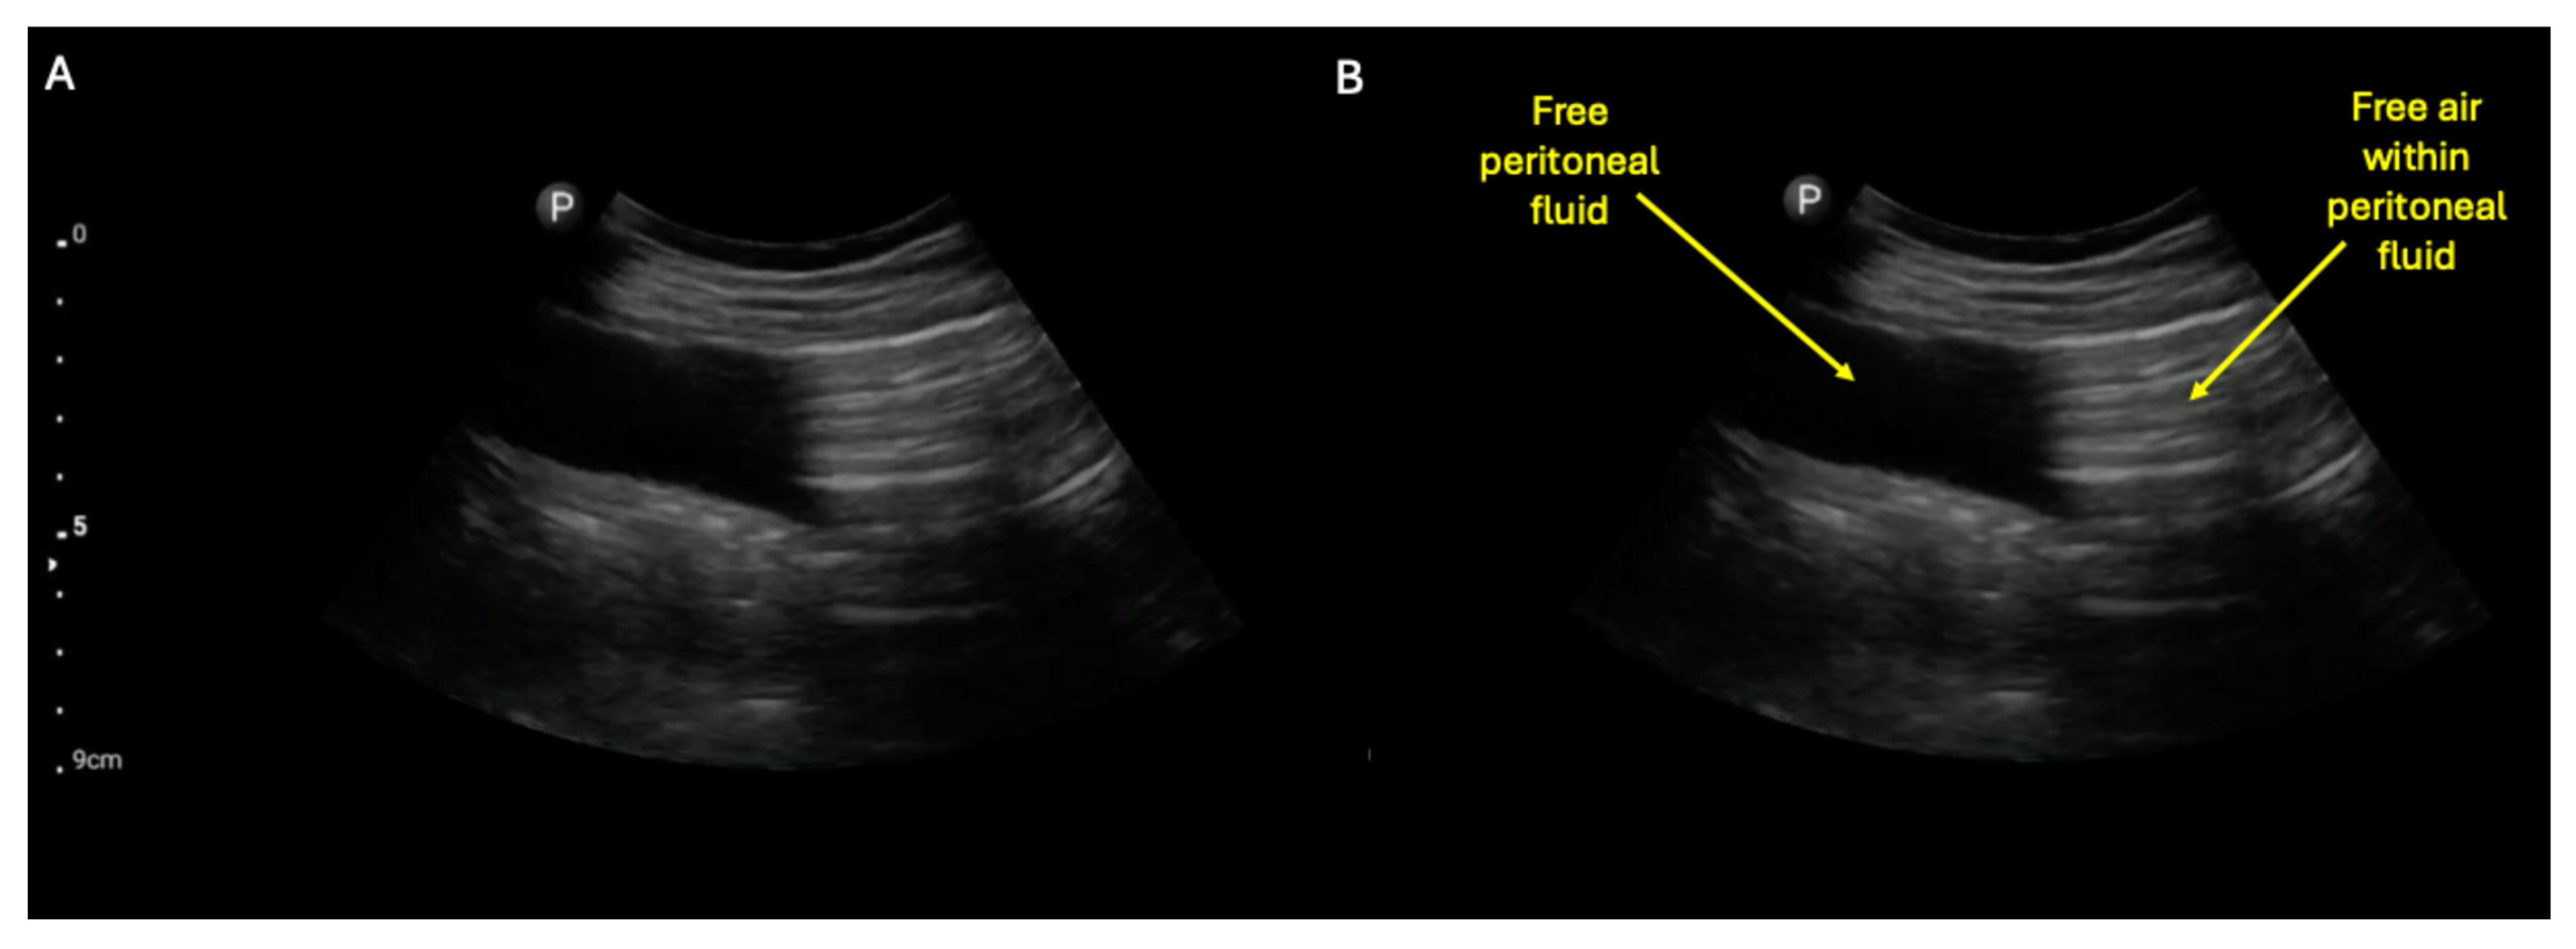

A possible complication of either SBO or ileus is small bowel perforation. The detection of a perforated hollow viscous by ultrasound has been previously described and shown to be diagnostically superior to plain film [14]. A highly suggestive finding is sonographic visualization of pneumoperitoneum within free peritoneal fluid, as shown in the unlabeled (A) and labeled (B) still images (see also Supplementary Video S4 to visualize dynamic movement of the air within the free peritoneal fluid) [14]. The finding of air within free peritoneal fluid is much more suggestive of pneumoperitoneum than just acoustic shadowing within the abdomen, which can be caused by air-filled loops of bowel alone (e.g., see Figure 6 and Supplementary Video S6).